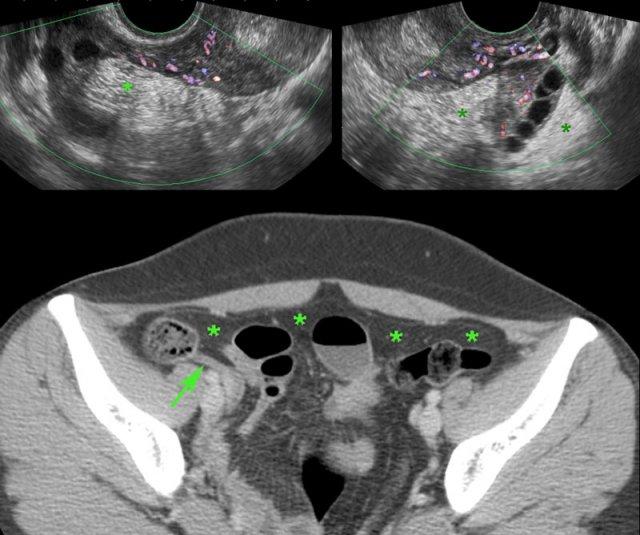

Phụ nữ trẻ với đau hố chậu phải cấp tính và CRP 140.

Siêu âm bụng hoàn toàn bình thường.

TVUS cho thấy hình ảnh tăng sinh mạch máu nhẹ ở cả hai vòi trứng và buồng trứng, được bao quanh bởi mô mỡ tăng âm, ép xẹp vừa phải (*).

Đây là hình ảnh của mô mỡ phúc mạc, mạc treo và mạc nối bị viêm nhẹ.

CT xác nhận ruột thừa bình thường (mũi tên) và hình ảnh tăng tỷ trọng lan tỏa nhẹ của mỡ phúc mạc, mạc treo và mạc nối (*).

Bệnh nhân hồi phục nhanh chóng với kháng sinh. Cấy vi khuẩn và PCR đều âm tính.